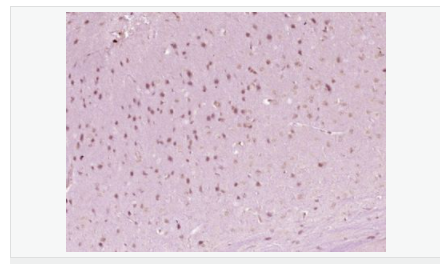

| 產(chǎn)品應(yīng)用 | WB=1:500-2000 ELISA=1:5000-10000 IHC-P=1:100-500 IHC-F=1:100-500 ICC=1:100-500 IF=1:100-500 (石蠟切片需做抗原修復(fù)) not yet tested in other applications. optimal dilutions/concentrations should be determined by the end user. |

| 產(chǎn)品介紹 | The Hox homeobox genes encode proteins that are transcriptional regulators with an established role in embryonic development. HoxA6 (homeobox A6), also known as HOX1B, is a 233 amino acid protein that localizes to the nucleus. Expressed during embryonic development, HoxA6 functions as a sequence-specific DNA-binding transcription factor that is part of a regulatory mechanism that provides cells with positional identities during development. Via its ability to bind DNA, HoxA6 plays an important role in the regulation of gene expression, as well as morphogenesis and differentiation. The gene encoding HoxA6 maps to human chromosome 7, which houses over 1,000 genes and comprises nearly 5% of the human genome. Defects in some of the genes localized to chromosome 7 have been linked to Osteogenesis imperfecta, Williams-Beuren syndrome, Pendred syndrome, Lissencephaly, Citrullinemia and Shwachman-Diamond syndrome. Function: Sequence-specific transcription factor which is part of a developmental regulatory system that provides cells with specific positional identities on the anterior-posterior axis. Tissue Specificity: Nucleus. Similarity: Belongs to the Antp homeobox family. Contains 1 homeobox DNA-binding domain. SWISS: P31267 Gene ID: 3203 Database links: Entrez Gene: 3203 Human Entrez Gene: 15403 Mouse Omim: 142951 Human SwissProt: P31267 Human SwissProt: P09092 Mouse Unigene: 679517 Human Unigene: 222030 Mouse Important Note: This product as supplied is intended for research use only, not for use in human, therapeutic or diagnostic applications. |